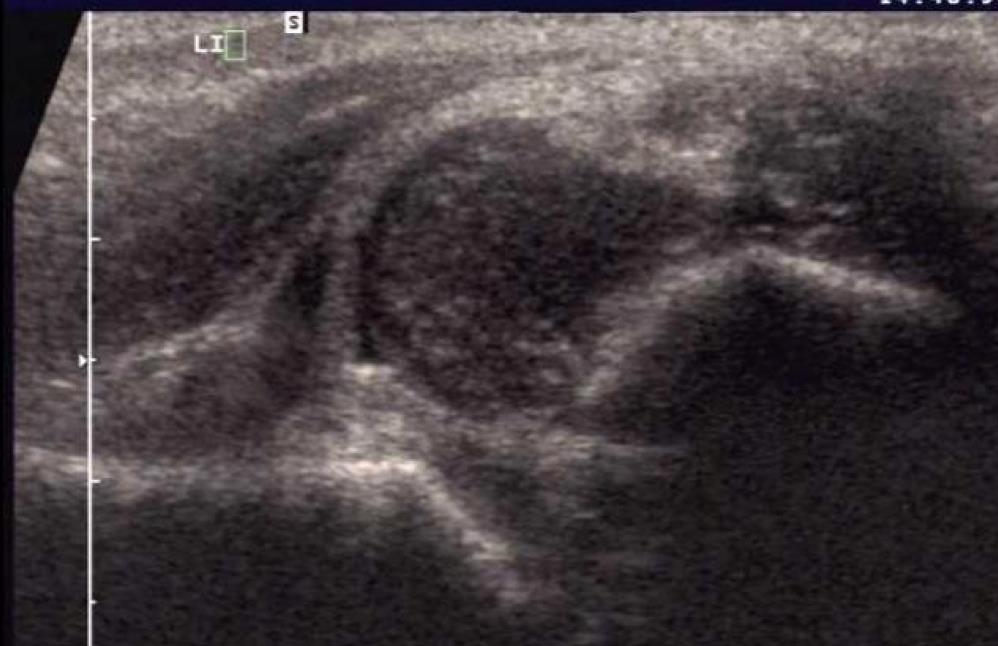

Diagnosis International Hip Dysplasia Institute Hip Dysplasia Orthobullets developmental dysplasia of the hip (ddh) is a condition where the hip joint does not form normally, causing the thighbone to be loose or dislocated in the socket. learn about the diagnosis and management of developmental dysplasia of the hip (ddh) in older children, who may require bracing,. a review article on the epidemiology, pathomechanism, diagnosis, and. Hip Dysplasia Orthobullets.